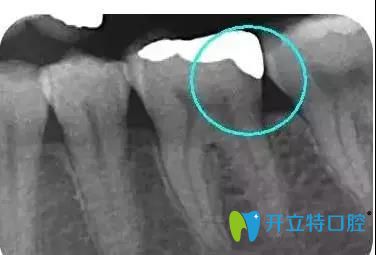

擅長(zhǎng)項(xiàng)目:種植牙、牙周病治療、牙體牙髓疾病診療、牙齒瓷貼面、瓷嵌體、全口活動(dòng)義齒、牙槽外科手術(shù)、各種復(fù)雜智齒的拔除等。

南昌輝煌口腔鄧云蟬醫(yī)生介紹嵌體補(bǔ)牙后注意事項(xiàng):